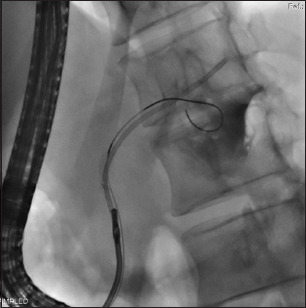

背景:胰腺支架近端移位是一个不常见但重要的问题,它会带来疼痛和胰腺炎的风险。对于内窥镜医生来说,这通常是一个具有挑战性的情况,10%的病例需要手术切除。方法:对2010年1月至2019年12月在印度北部一家三级医疗中心进行的支架移除手术进行了10年的回顾性研究。结果:本组共16例(平均年龄39.52岁,男性13例[81.25%])行近端移位胰内支架(pmps)。13例(81.25%)患者胰管扩张,3例(18.75%)患者胰管未扩张。在大多数患者中,pmps位于膝(50%),62%长度为10 cm。3例(18.75%)患者支架碎片化,其余13例(81.25%)患者支架原位完整。12例(75%)患者可以完全取出PPMS和支架碎片,大多数(50%)患者使用抓钳。在支架碎片化和定位困难的患者中(n=3),胰镜辅助技术可将支架或碎片取出。3例患者pmps无法检索:所有这些失败都发生在我们单位没有SpyGlass胰镜的研究期间。2例患者(12.5%)报告术后疼痛对静脉镇痛药有反应。结论:内镜下取下近端移位支架,结合技术和附件是安全有效的。胰镜检查提高了成功率。支架移除很少需要手术。

Results: Sixteen patients (mean age 39.52 years, 13 [81.25%] males) with proximally migrated pancreatic stents (PMPSs) were studied. Thirteen (81.25%) patients had a dilated pancreatic duct (PD) and 3 (18.75%) had a non-dilated PD. In the majority of patients, the PMPSs were located at the genu (50%), while 62% were 10 cm in length. Three (18.75%) patients had fragmented stents, whereas the remaining 13 (81.25%) had intact stents in situ. Complete retrieval of the PPMS and stent fragments was possible in 12 (75%) patients, with grasping forceps being used in the majority (50%). In patients with fragmented stents and difficult locations (n=3), pancreatoscopy-assisted techniques resulted in the retrieval of the stent or fragments. PMPSs could not be retrieved in 3 patients: all these failures were during the study period when a SpyGlass pancreatoscope was not available in our unit. Two patients (12.5%) reported post-procedural pain that responded to intravenous analgesics.